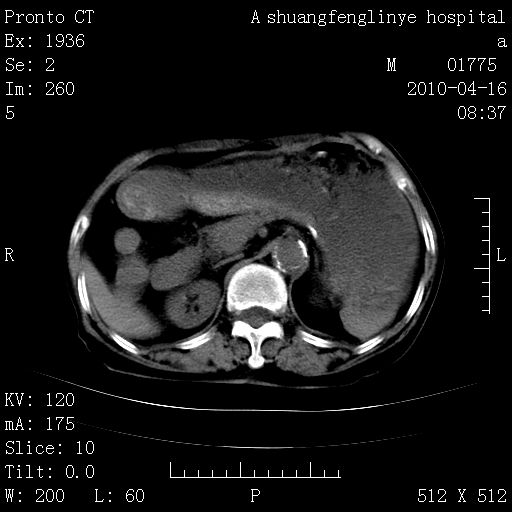

标题: CT25784:咳痰、请会诊!结核?

陈旧性结核,胃腔扩大,脾脏受压后移

慢支肺气肿,左上陈旧性结核,主动脉冠脉钙化

典型 夹层动脉瘤。 内膜瓣钙化移位

1)左肺上叶结核(纤维、增殖病灶)。2)冠状动脉及主动脉钙化。

1)左肺上叶结核(纤维、增殖病灶)。2)冠状动脉及主动脉钙化。肺动脉高压